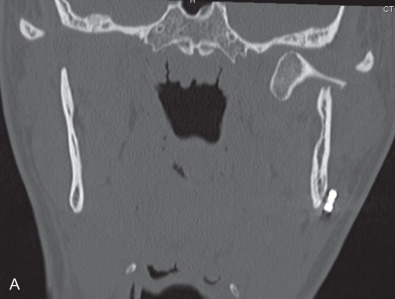

All of these systems allowed for convalescent function – life without MMF. RIF had the potential of dramatically shortening the course of treatment. However, its use was highly technique-sensitive with a steep learning curve. Thus, the incidence of complications increased dramatically due to operator error. Complications related to inadequate reduction – “the OIF” (open internal fixation … without the reduction) ( Figs. 1.16.1–1.16.3 ), inadequate fixation ( Figs. 1.16.4–1.16.7 ) and surgical misadventure ( Fig. 1.16.8 ) began to appear. Indeed, by the early 1990s operator error was the number one cause of mandibular fracture complications. Quite obviously, RIF is very unforgiving. When done poorly, one has a rigidly fixed mistake. The latest series of misadventures are related to the use of IMF screws. Bone-anchored arch bars will most likely be next. Not all believe that RIF and convalescent function is cost-effective with respect to the increased cost, potential for complications, and patient acceptance.